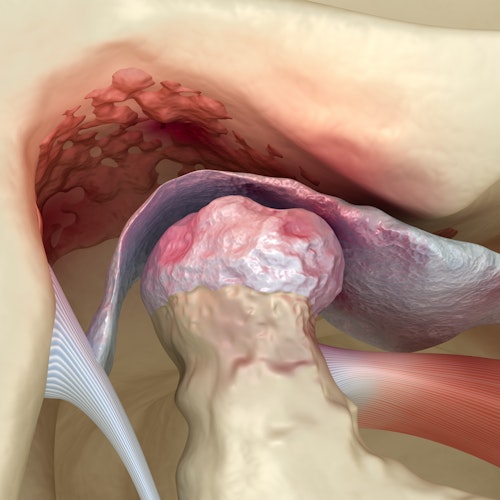

The Temporomandibular Joint: A Small But Crucial Part of Your Jaw

Many Patients Do Not Realize The Effect TMJ Disorders Can Have on Their Teeth

While our teeth can withstand a fair amount of pressure, they're not invulnerable.

Over time, TMJ disorders can damage your back teeth. The action of clenching or grinding your TMJ can cause cracks, chips, or other breakage. It may also cause your back teeth to become worn from all the pressure.

Finally, your teeth may feel loose, which can be uncomfortable and stressful.

Typical hallmarks of TMD include clenching, jaw tightness, and headaches. However, not every patient presents with these symptoms. If you think you may have TMD, our dentists can examine your mouth and determine the cause of your discomfort. They will then develop a treatment plan to ease your pain and prevent further oral health concerns like damage to your teeth.

Headaches, jaw aches, and even earaches — life with TMD can mean daily pain.

Some patients even experience difficulty opening and closing their mouths due to inflamed TMJ joints, making it hard for them to eat or talk.